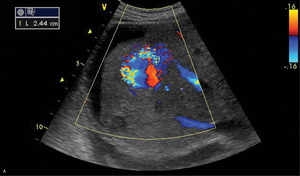

Optymalną metodą w rozpoznawaniu przyczyny nadciśnienia wrotnego jest color doppler. Jest to metoda tania, nieinwazyjna i powszechnie dostępna. Umożliwia przy tym wszechstronną ocenę: uwidacznia zarówno zmiany miąższowe, jak i zaburzenia przepływu w naczyniach (skrzepliny w obrębie naczyń, uciśnięcie naczyń lub nacieczenie przez rozrost nowotworowy; daje możliwość uwidocznienia dróg krążenia obocznego, naczyń tętniczych, żył wątrobowych i krążenia wrotnego). Pulsed wave doppler pozwala na ocenę kierunku i charakteru przepływu: uwidocznienie naczyń i przetok tętniczo-żylnych jest bardzo dobre (ryc. 1).